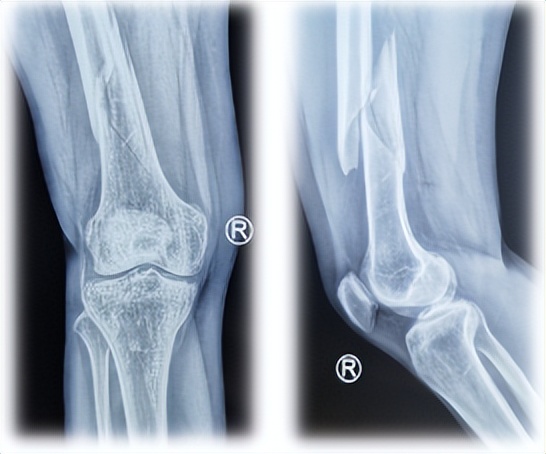

初次骨折X线片

骨不连X线片

骨不连第1次手术失败

骨不连第2次手术失败

骨创伤医院下肢病区李忠主任接诊后,结合X线片、受伤机制、既往史、前2次手术方式、骨骼情况及软组织情况,评估RUSS评分65分,手术难度较大,且杨女士已经历3次手术, 存在严重的恐慌心理,因此手术不能出差错。